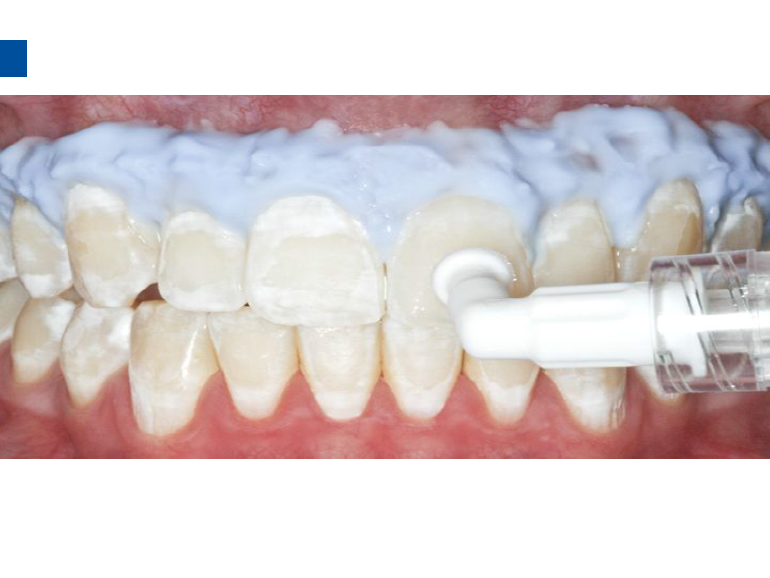

lcon渗透基于封闭釉质龋空隙的一种特殊树脂的渗透,封闭釉质龋小孔,从而阻断致龋酸传播途径,阻止龋病进一步发展。这种材料操作方法简单,对牙体组织损伤轻微,不用通过麻醉和磨切牙体来达到加固脱矿釉质,同时可以改变釉质龋表面的白色或棕色改变,达到美观修复效果,是对龋病微创治疗的突破。

7、旋转注射器柄部将足量材料涂布于已被酸蚀的龋损表面之上,等待3分钟,并用棉球去除多余材料。不要在牙椅照明灯直射下在前牙唇面涂布树脂。)